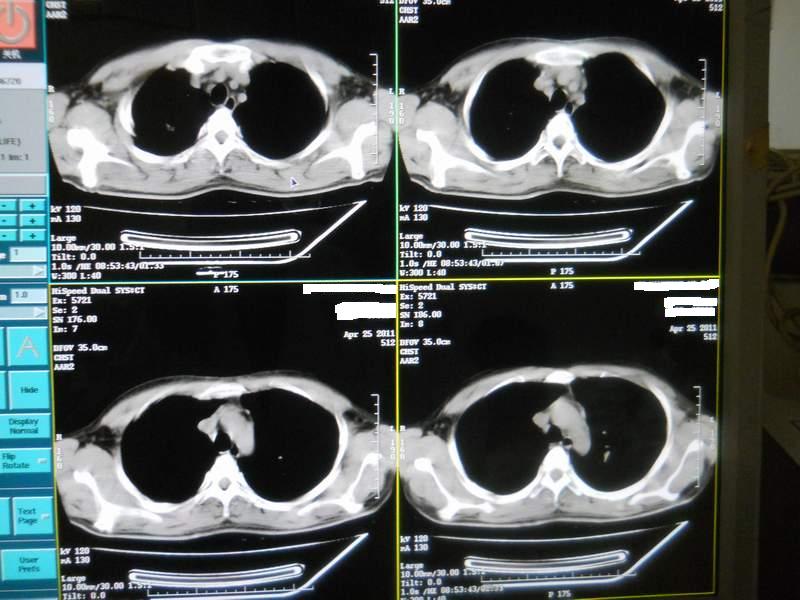

肺霉菌感染

男,22岁,一年前诊断马尔菲尼青霉菌感染,多次复查CT。多次HIV阴性。最近两次CT图片。有实验室结果。

最近实验室检查结果:霉菌感染。